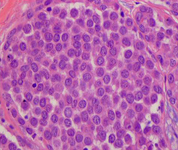

Histopatología del carcinoma lobular in situ (CLIS) pleomórfico

Cortesía del Dr. Sunati Sahoo, University of Louisville; utilizada con autorización

Ver esta imagen en el contexto de la/s siguiente/s sección/es: